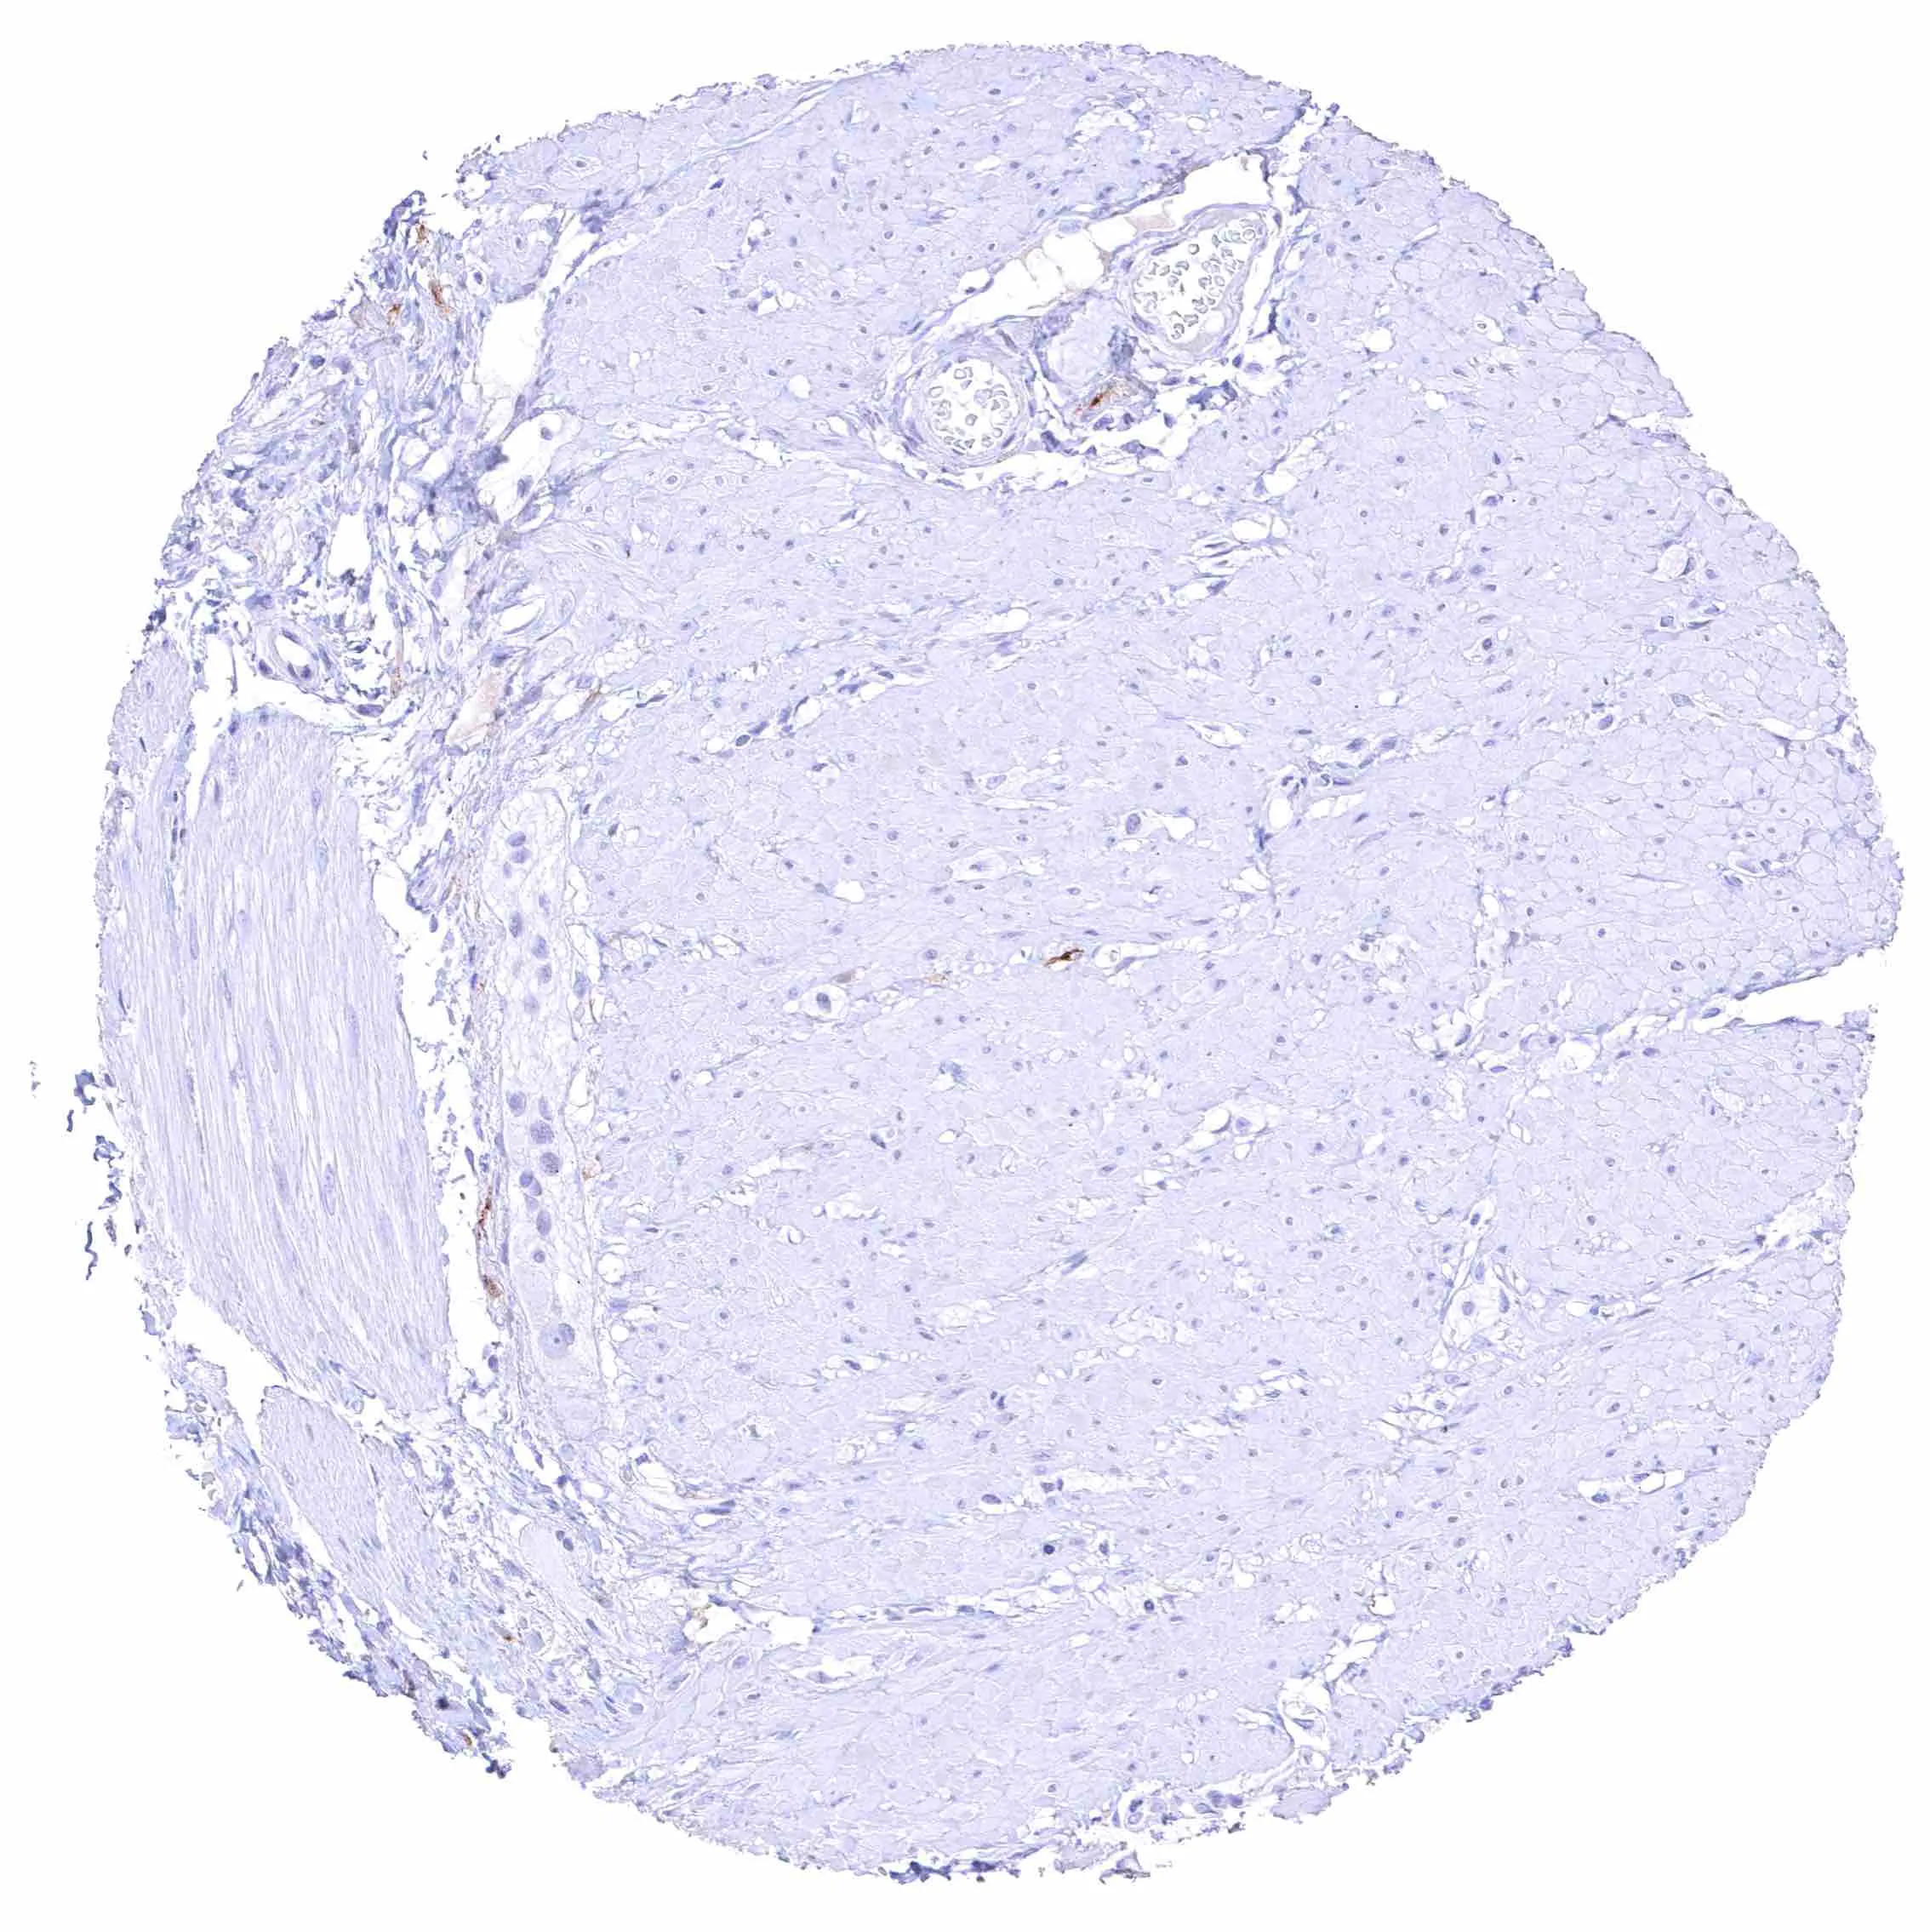

Uterus, myometrium – Distinct NPR-C staining of endothelial cells in some but not all blood vessels